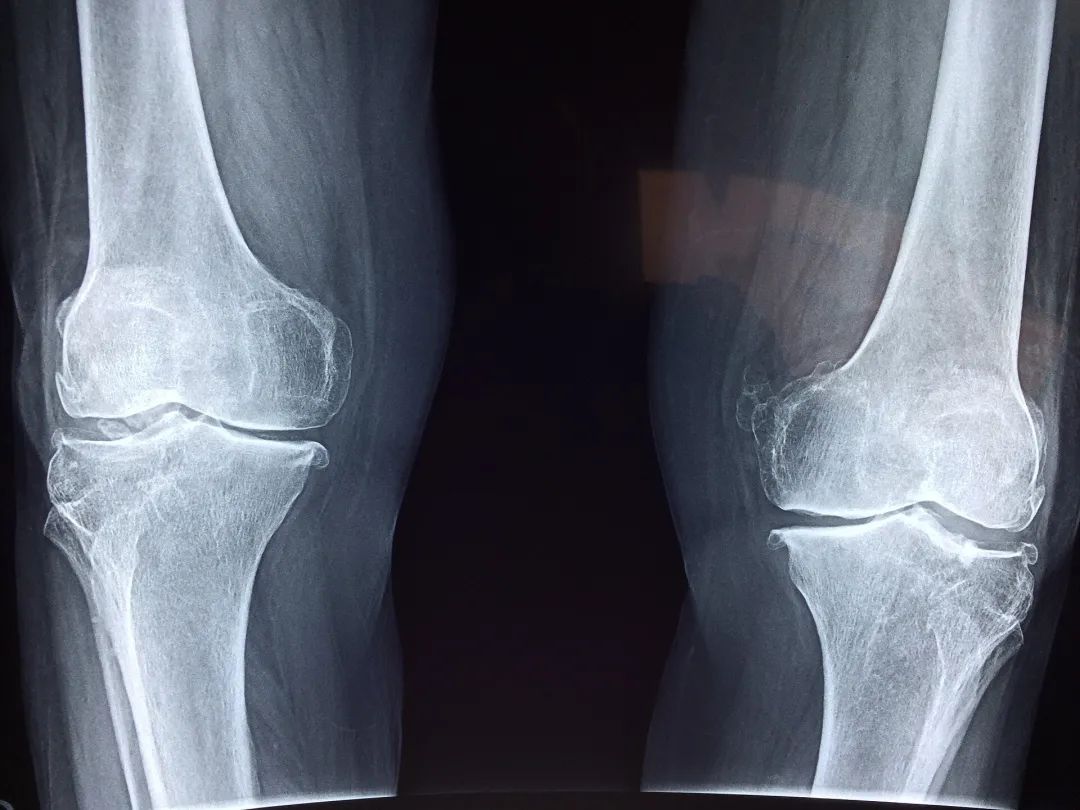

术前检查的膝关节x线

图片尺寸2000x2667